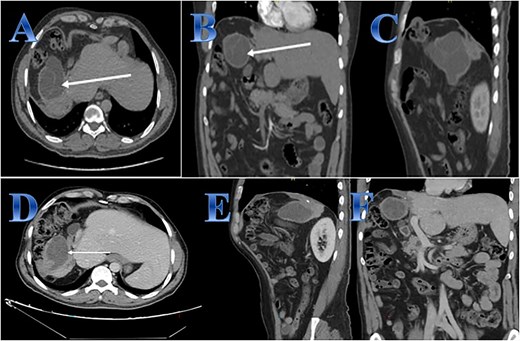

A 53-year-old female presented with epigastric dull aching pain, with nausea and mild epigastric tenderness. Abdominal CT described three large hepatic CE with mass effect on the intrahepatic IVC (Fig. 5).

Case 5. (A, B, C & D) Three large hepatic cystic lesions seen, the largest two lesions seen at the hepatic dome and right hepatic lobe seen non-separable from each other, showing peripheral coarse calcifications (photo A), the lesions seen abutting and exerting mass effect on the intrahepatic IVC (photo D). One lesion seen exophytic superiorly to the subdiaphragmatic region elevating the right hemidiaphragm (photo C), the second lesion exophytic inferior posteriorly (photo B). (E) The content of the cyst in liver segment 8 after opening the cyst and aspiration. (F) Area of liver segment 4 after complete resection of the cyst after cholecystectomy. (G) Area above tow cysts in liver segment 7 & 8 after complete separation from diaphragm and resection of the cysts.

The patient received albendazole treatment with clinical improvement. Three months after treatment, laparoscopic peri-cystectomies were done with the removal of the covering parenchyma. During exploration, there were three large cysts; the first one was in liver segment 4a, extending to liver segment 8, compressing the intrahepatic IVC; the second one was adjacent to the first one, extending from liver segment 8 to segment 7 and the third one was in liver segment 4b extending to segment 5 and adjacent to the gallbladder. The liver mobilization was done by detaching the right triangular ligament and coronary ligament, which were fixed to the upper two cysts’ upper border, to mobilize the right liver lobe, then cholecystectomy was done. A suction device was used to puncture the cyst and aspirate the cyst fluid. The pericyst is carefully opened; the germinal layer and hydatid sand are removed using laparoscopic forceps and suction devices (Fig. 5).